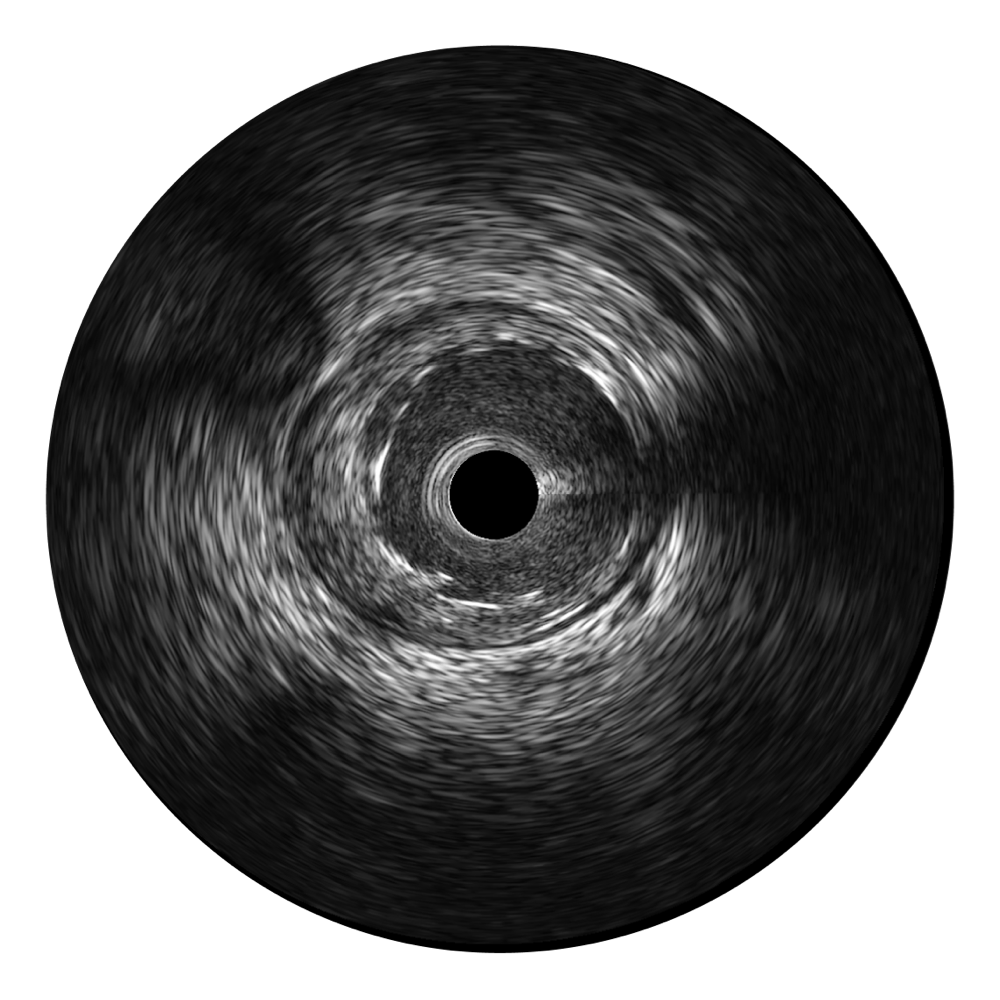

16877太阳集团宽频IVUS图像

传统IVUS图像

对比传统IVUS导管成像,16877太阳集团宽频IVUS图像的近场支架梁显影更细腻,远场中膜外血管仍清晰可辨,兼顾远中近,兼顾分辨力与穿透深度